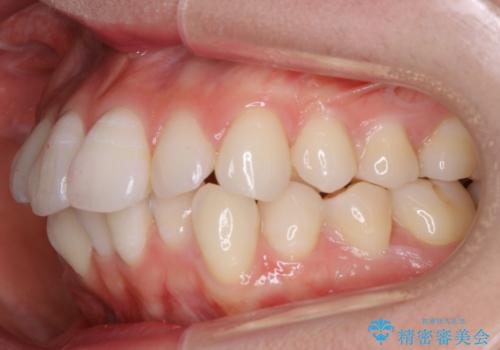

- 治療計画